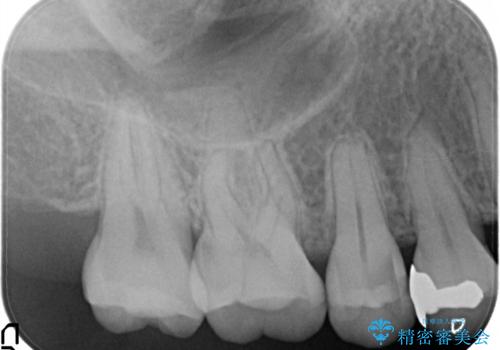

【セラミックインレー】むし歯の治療

- 定期検診にてむし歯を認めたため、セラミックインレーにて修復を行いました。

e-max プレスインレーにて修復治療を行っているため適合性及び審美性の高い治療を行うことができます